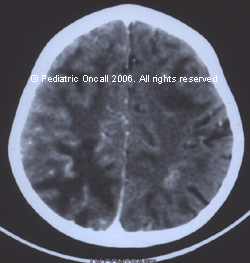

An HIV infected child presented with convulsions and unconsciousness. There was no neck rigidity and contact with tuberculosis.

CNS toxoplasmosis. Although no single CT appearance can be considered pathognomonic for CNS toxoplasmosis, multiple ring like or solid, rounded areas of enhancement often can be seen on contrast enhanced CT. Although no anatomic location is considered classic, involvement in the region of the basal ganglia and other surgically inaccessible areas (e.g., the midbrain and brainstem) is common. Occasionally asymmetric target lesion has been identified in patients with toxoplasmosis. In the immunocompromised AIDS patient, a thick rim of enhancement on CT is less common than in other patients